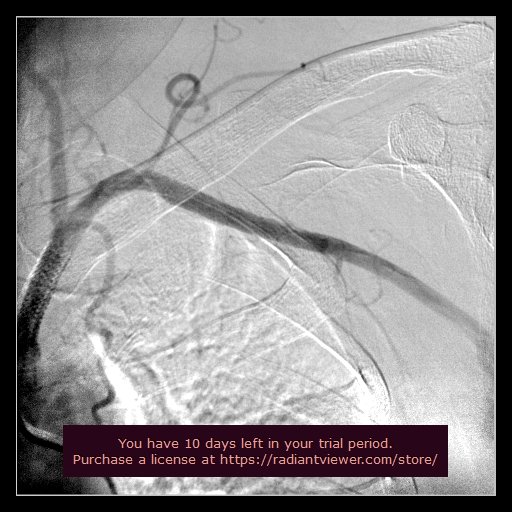

BRONCHIAL ANGIOGRAPHY